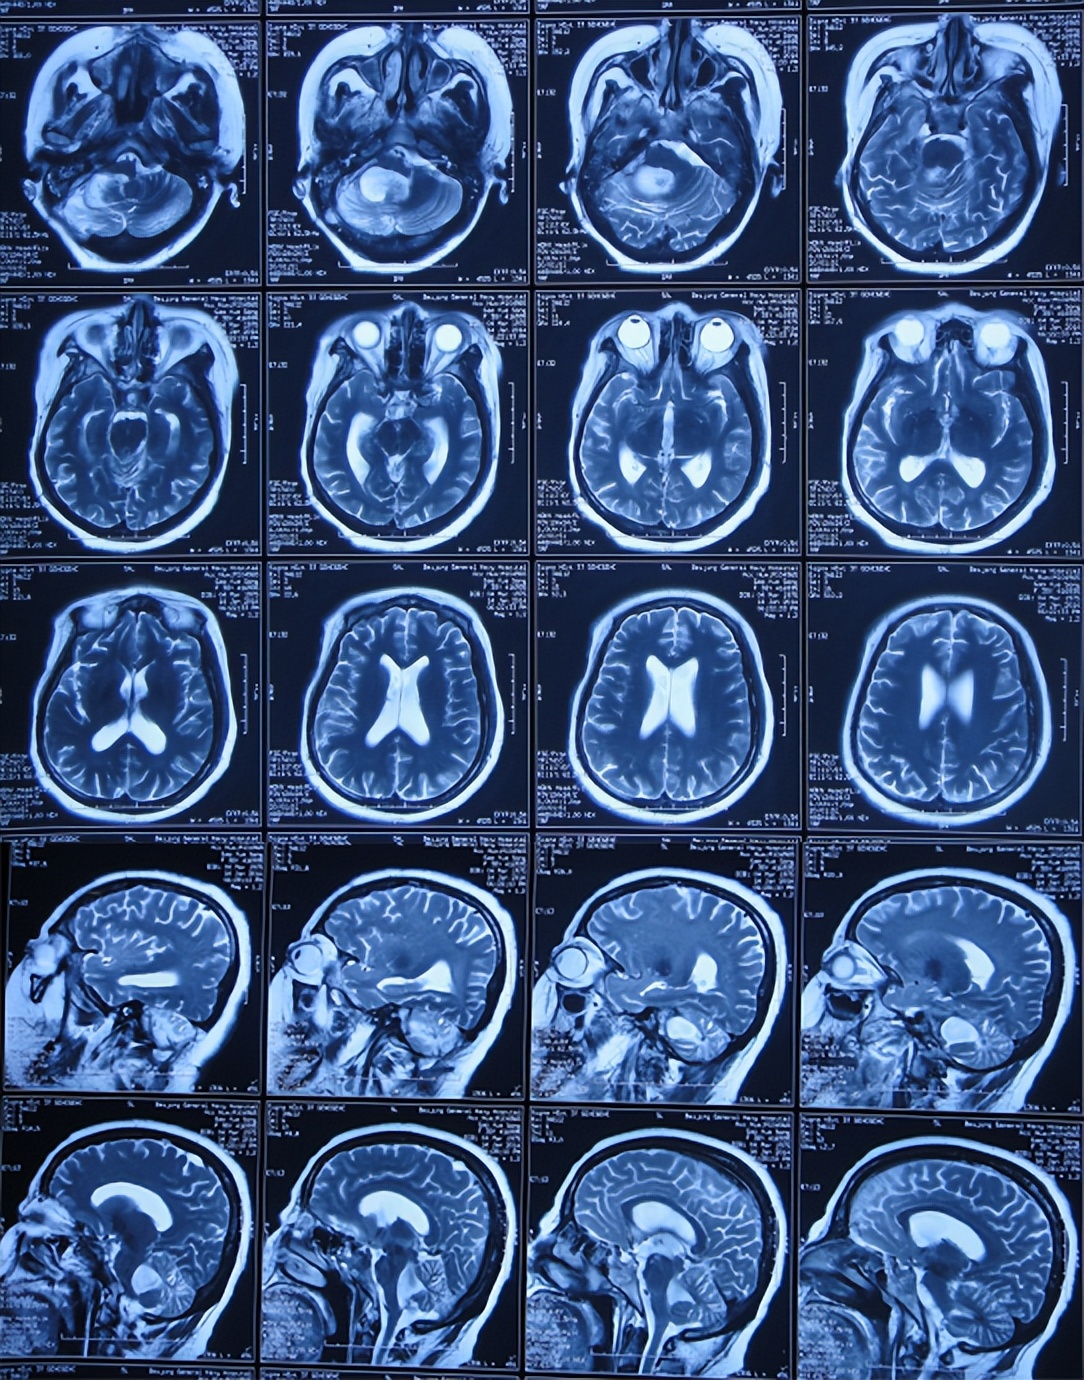

当天转至上级的山西省某省级三甲医院,查头颅核磁(图-2)示听神经瘤,需要手术。

图-2:2013年11月6日头颅核磁和核磁增强

腰大池引流术后10天即2013年12月1日(听神经瘤切除术后17天),仍反复发热(停止鞘内注射后2-3天再次出现发热),查头颅核磁增强(图-5)出现硬膜下积液。

图-5:2013年12月1日头颅核磁增强

听神经瘤术后61天即2014年1月14日,已持续交替腰大池引流、腰穿治疗并联合鞘内注射循环5次),但仍间断发热,脑脊液培养发现真菌,查头颅核磁增强(图-10)后给予鞘内联合静脉两性霉素抗真菌治疗。

图-10:2014年1月14日头颅核磁增强

2014年3月14日即听神经瘤术后120天,查头颅核磁增强示四脑室有扩张(图-12)。

图-12:2014年3月14日头颅核磁增强